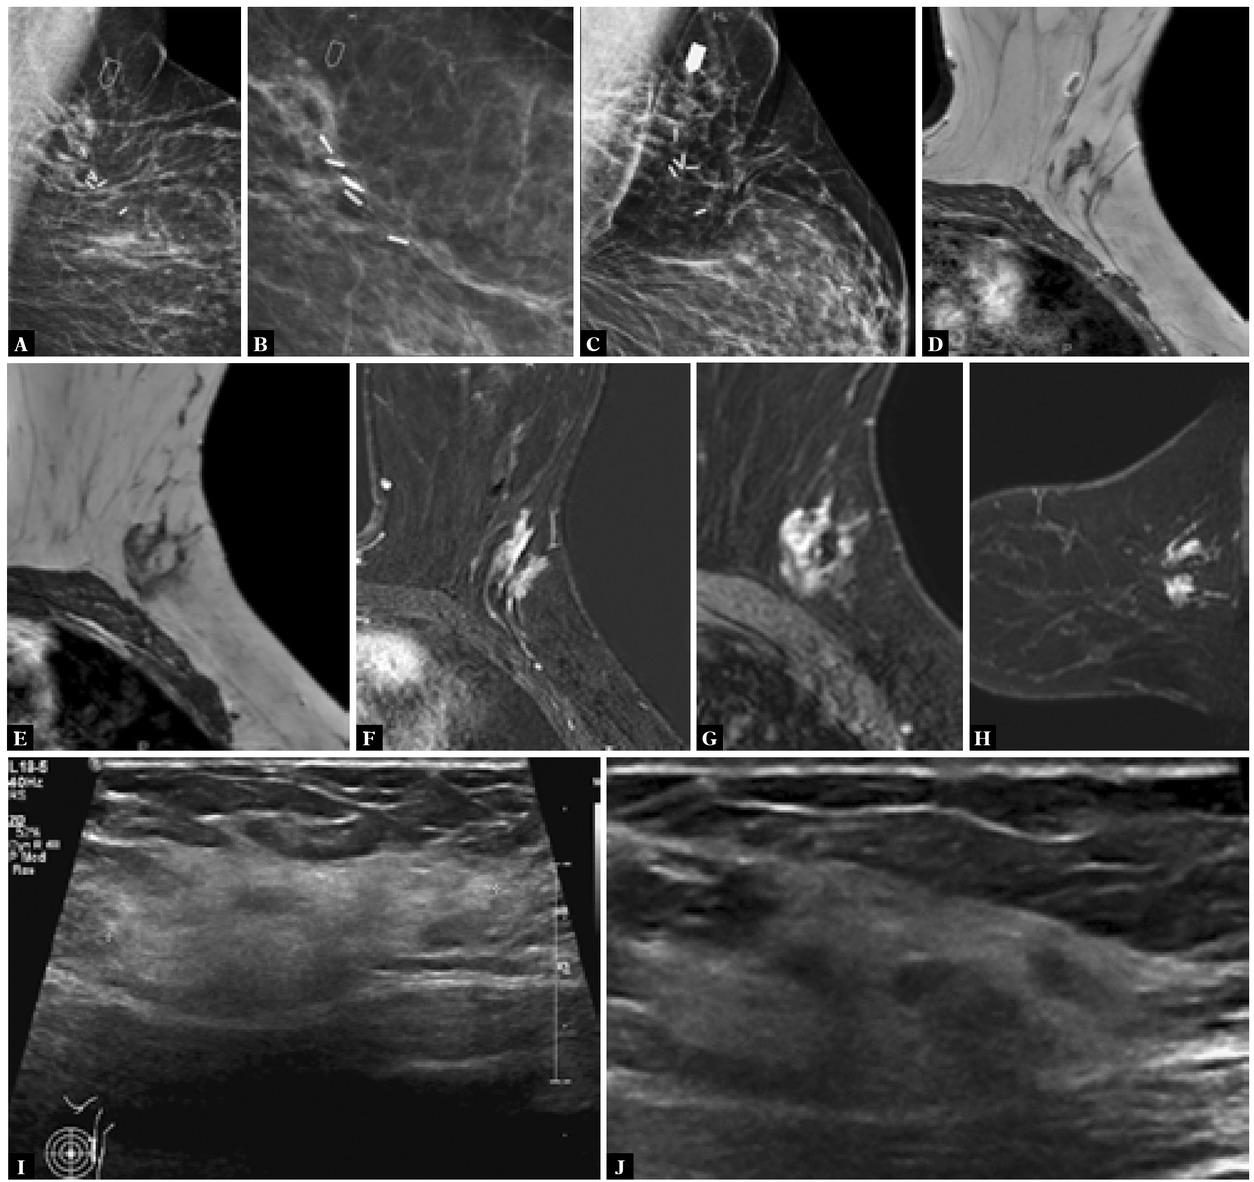

Fig. 3

A. MLO mammogram. B. Magnification views shows post-operative scarring in the upper outer left breast with surgical clips. New developing focal asymmetry at (arrow) just lateral to the scar. C. Post biopsy mammogram shows the clip (solid arrow). MR images T1W axial images (D, E), MR axial subtracted post-contrast images (F, G) and reconstructed sagittal post-contrast MR image (H) show post-operative surgical clip and adjacent architectural distortion with enhancement (I, J). Ultrasound image shows a large heterogeneous hyperechoic mass in the outer mid and upper left breast, with visible small regions of hypoechoic shadowing